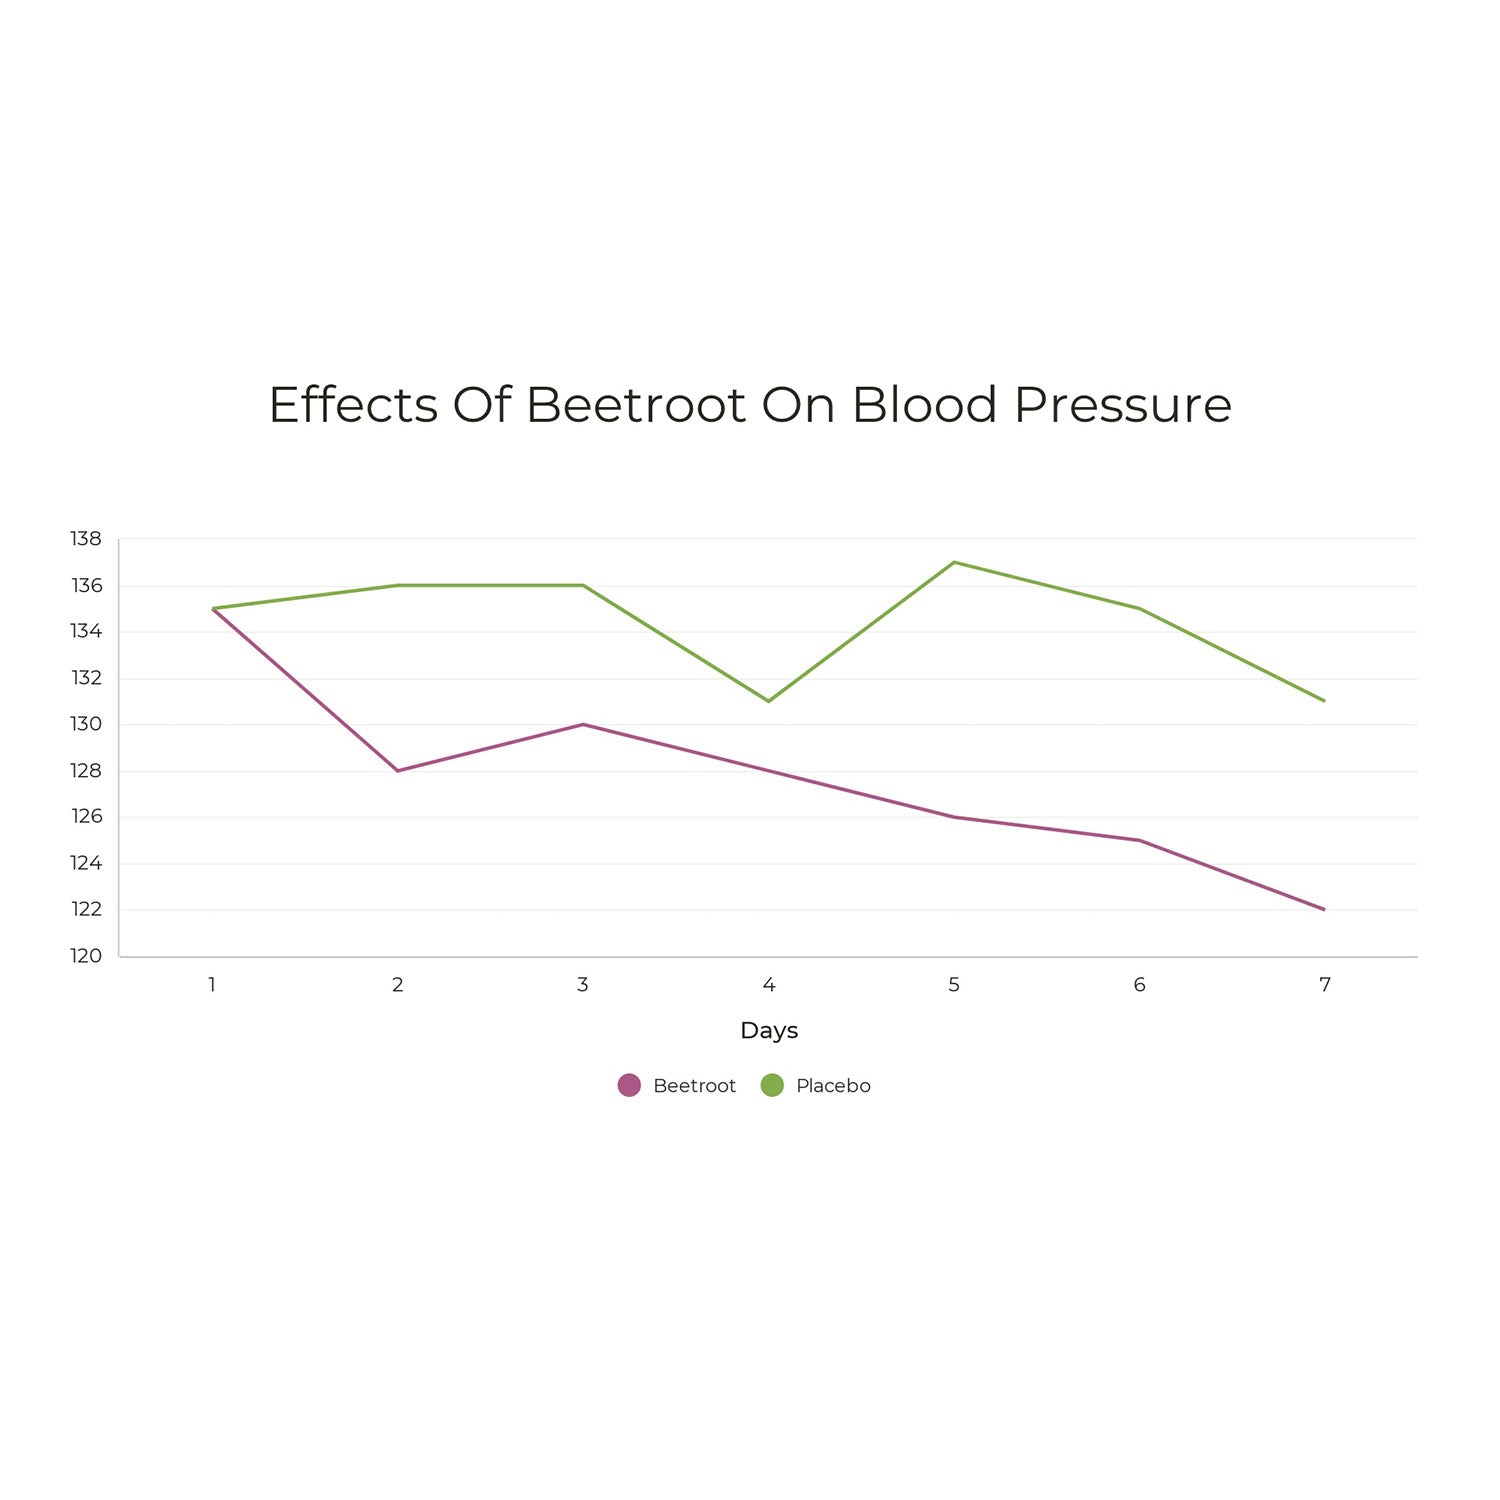

NUMEROUS SCIENTIFIC STUDIES HAVE OBSERVED LOWER BLOOD PRESSURE AND IMPROVED BLOOD FLOW AFTER BEETROOT SUPPLEMENTATION

As reported by the British Heart Foundation, beetroot has been correlated with significant reductions in blood pressure & chronic inflammation in clinical trials

Many clinical trials of beetroot supplements have observed significant reductions in systolic and diastolic blood pressure. One study even observed reductions in blood pressure similar to a single dose of a anti-hypertensive drug at a standard dose.